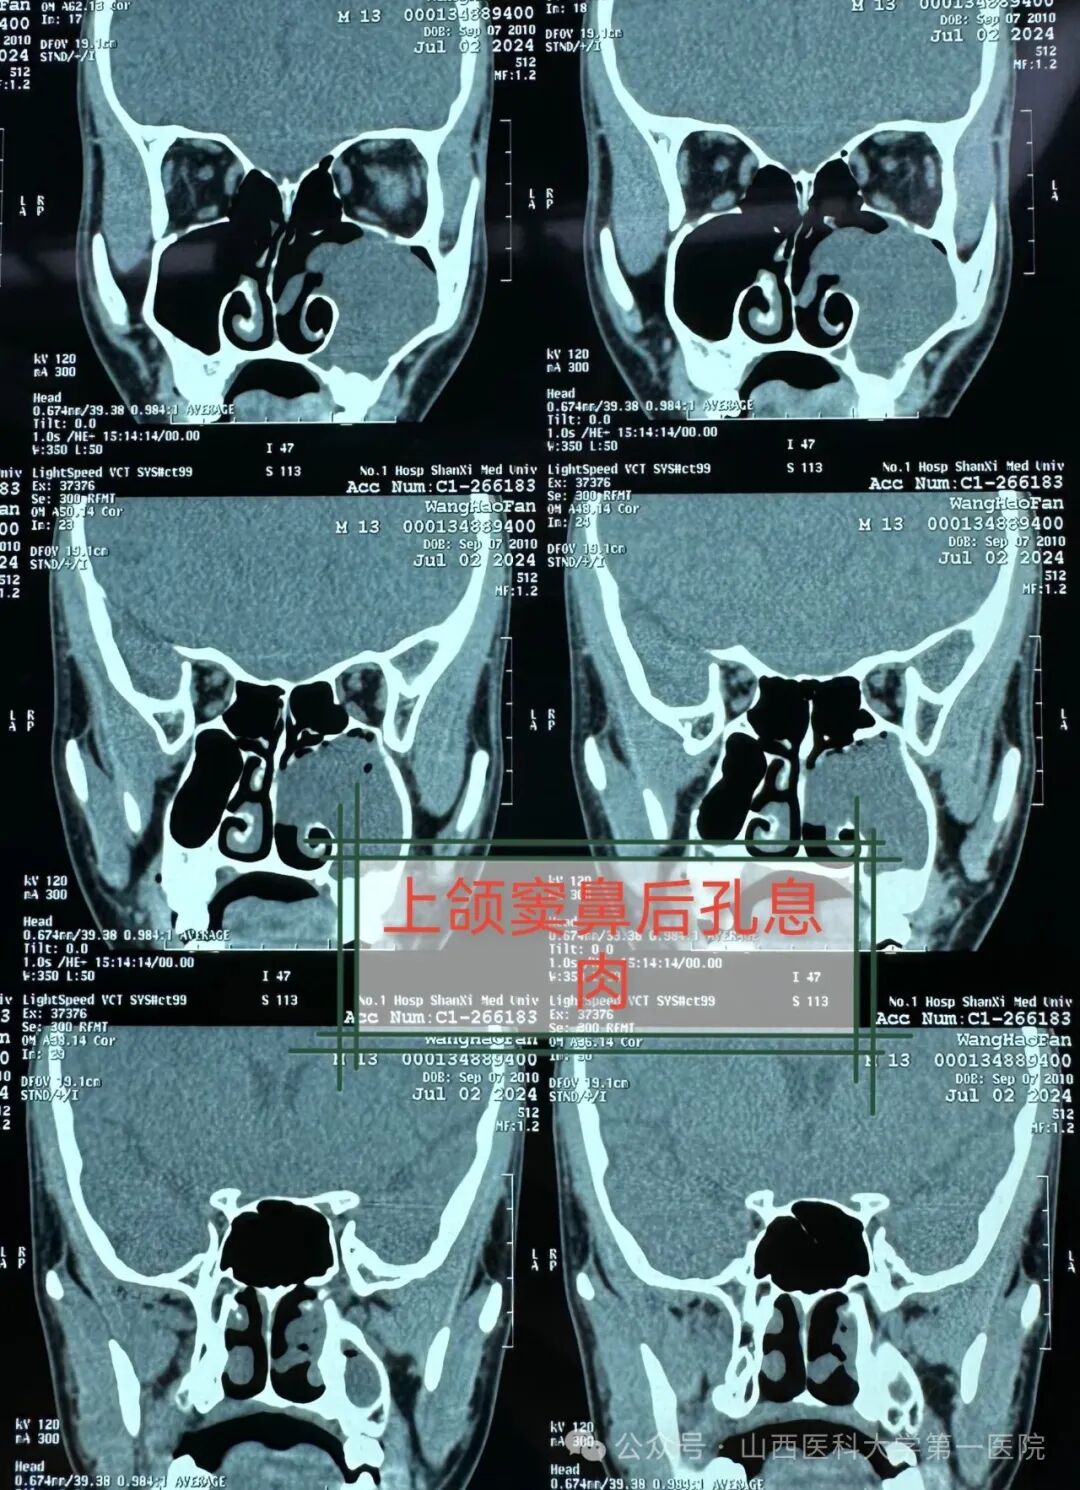

通过检查发现单侧鼻腔多量淡红色荔枝肉状肿物完全堵塞鼻孔,鼻窦轴位与冠状位CT示鼻腔及上颌窦充满低密度影,鼻腔鼻窦占位性病变,初步考虑为鼻腔鼻窦息肉,而鼻腔鼻窦息肉是一种良性病变,易复发、不易恶变,治疗关键是手术完整彻底切除病变。